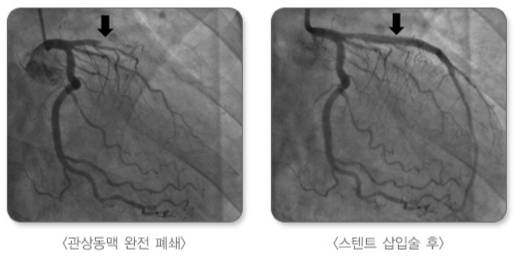

응급실에선 심전도·혈액 검사로 심근경색 여부를 진단한다. 심근경색으로 진단하면 막힌 혈관을 풍선·스텐트로 뚫는 '관상동맥 중재술'을 시행한다. 심장성 쇼크나 심정지 상태로 내원한 경우에는 에크모(ECMO, 체외막형산소화요법) 등 기계 순환 보조 장치를 이용해 심장·폐 기능을 일시적으로 대신하며 치료한다.